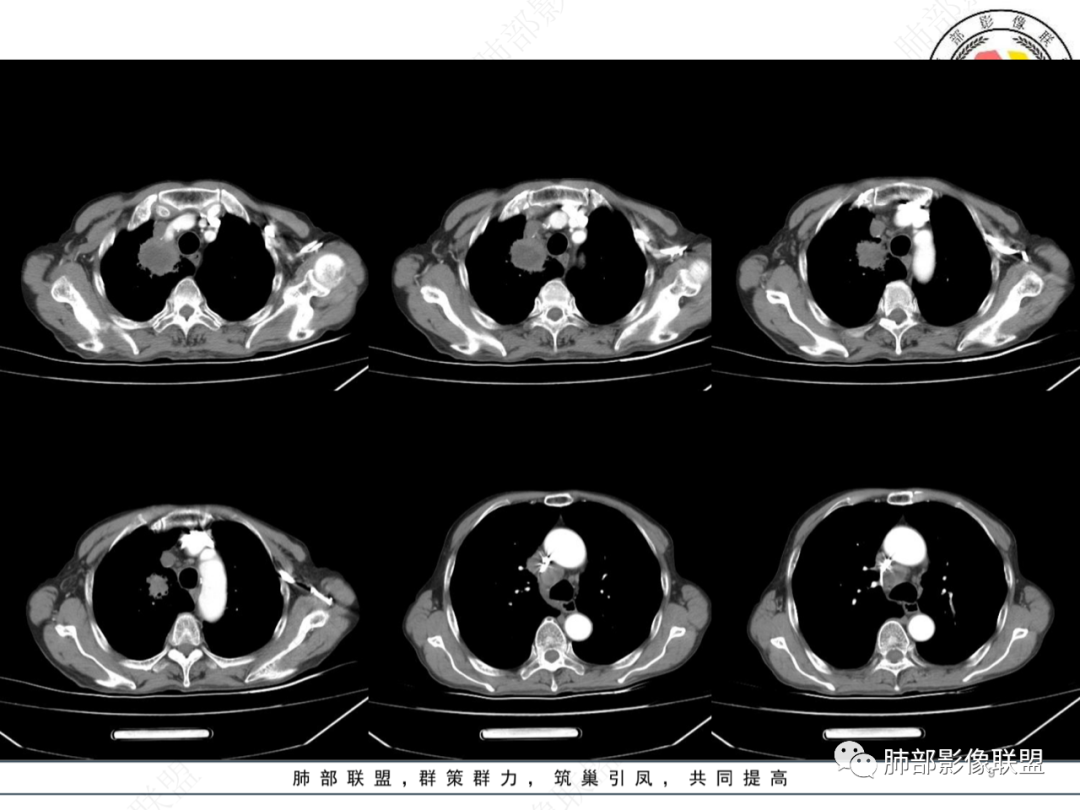

右肺上叶尖段团块影,中央见大片状状坏死伴液气平面,周围见斑片状高密度影,实验室检查血象明显升高,抗炎治疗后,病灶有所吸收缩小,灶周斑片状消失,考虑肺脓肿,鉴别鳞癌伴感染。

右肺上叶尖段团块,密度不均,中央见坏死区,坏死边缘清晰,气管堵塞,周围见斑片状高密度影,血象明显升高,治疗病灶有所吸收缩小,考虑肺脓肿,鉴别鳞癌。

右肺尖团块,边缘模糊,支气管截断,环形强化,内部大片坏死,抗炎后复查出现液平,考虑恶,鳞癌伴肺脓肿,鉴别结核。

体温39度,白细胞显著升高。右肺上叶团块,边缘毛糙,其内近心侧大面积液化坏死,病灶相近内侧肺内见淡片影,增强渐进式轻度强化,坏死边缘较清晰。纵隔2组及4组淋巴结环形强化,边界清晰无融合,与肺病灶同源。一月后复查病灶出现破溃形成气液平,周围渗出,胸腔积液。先考虑感染性病变,结核,脓肿。恶性病变待排。

右肺上叶占位,气液平面,坏死内外壁光滑,上叶后段还有一小病灶,纵隔肺门淋巴结肿大坏死,环形强化,血象高,考虑肺脓肿,鉴别肿瘤,肺梗死。

右肺尖占位病变,边缘膨隆,内坏死,内壁厚薄不均,纵隔分界不清,血管壁似受侵及,纵隔淋巴结肿大,考虑恶性鳞癌可能。

右肺尖不规则肿块伴炎症,分叶、棘突,支气管截断,坏死明显,纵膈淋巴结肿大伴坏死,一月复查肿块出现液平,周围渗出,治疗2周复查液平及周围炎症吸收,肿块未见明显吸收,考虑肿瘤伴感染,鉴别肺脓肿

右肺尖肿块,支气管截断,内部坏死,纵膈淋巴结肿大伴坏死,上腔静脉内似有低密度影,治疗后复查空洞形成,主病灶无明显变化。考虑恶性。

右肺尖团块状占位,可见支气管截断,增强呈轻度环形强化,纵隔可见肿大淋巴结,亦呈环形强化,1个月后,病变内部可见气液平,边缘可见斑片状影,治疗后,周围病变吸收,占位性病变少变小,右侧少量胸腔积液,常规考虑肺脓肿,鉴别鳞癌伴发脓肿。

右肺上叶肿块,其内见液化坏死,增强实性部分明显强化,坏死边缘较清晰,纵隔淋巴结环形强化,与肺内病灶相似;一月后复查形成气液平,周围渗出,胸腔积液;考虑感染性病变,结核、脓肿,不除外鳞癌合并感染

男性,发热咳嗽咳痰,炎性标志物显著升高,急性病程,右上叶结块,边界不清,可见支气管截断征,结块内坏死边界清,内可见分格,坏死壁厚薄不均,均匀强化,似可见壁结节,治疗后见液平及悬浮气泡,纵隔内淋巴结肿大,综合分析,首先要考虑鳞癌并感染,其次肺脓肿或放线菌。

首诊,右肺上叶尖段肿块伴坏死,纵隔淋巴结肿大并坏死,坏死边界不光整,后续肿块坏死增加并积气,灶周新发感染,考虑鳞癌合并感染,鉴别肺脓肿

右肺上叶高密度影,边缘模糊,内密度不均匀,部分支气管截断,增强后不均匀强化,内可见片状坏死无强化,纵隔多发肿大淋巴结不均匀强化,短期复查脓肿形成,并远端阻塞性炎症,抗炎治疗后脓肿及炎症有吸收,考虑恶性,鳞癌伴纵隔淋巴结多发转移

右肺上叶软组织密度肿块影,边界清晰,病灶内见坏死,增强扫描病灶呈不均匀性强化,右肺上叶支气管变窄,纵隔内见肿大淋巴结,考虑恶性病变鳞癌伴纵隔淋巴结转移可能,鉴别肺脓肿。

右肺上叶纵隔软组织密度影,边界相对清晰,病灶内见低密度坏死区及分隔,增强后肺尖处实性成分中等强化,并见明显透彻坏死区且坏死边界清晰,纵隔一肿大淋巴结中心坏死,增强后环形强化。还是优先考虑肿瘤性病变,白细胞中性很高,继发感染可能,鳞癌?鉴别肺结核,慢性肺脓肿。

右肺上叶肿块伴坏死,纵隔淋巴结增大并坏死,右肺上叶支气管狭窄。第一次复查肿块内气液平形成,周边阻塞性炎症,右侧胸腔积液,第二次复查炎症吸收减少。考虑肿瘤并感染?鉴别肺脓肿。

主病灶在右上叶尖段、前段纵隔旁,紧贴胸膜

楔形、边缘膨隆,附近见斑片状、网格状高密度影

支气管近端堵塞,可惜显示的不一定全面

支气管壁还是弥漫增厚

中央坏死明确

整体内壁偏清楚,似乎有些地方欠清,不知道是否厚层所致

整体而言:远侧、内侧壁厚

坏死明显,这类膨隆就不支持生长速度不一致所致,而支持坏死朝周围的压力导致边缘的膨隆

患者有高血压、脑梗死、肾结石病史,因左胸痛不适入院,伴高热,血常规示白细胞、中性粒细胞高。胸部CT示右肺上叶肿块影,边缘模糊影,内可见低密度坏死,边界清楚,一月后出现气液平面,周围渗出,治疗2周复查液平及周围炎症吸收,肿块未见明显吸收。

考虑肿瘤?右肺上叶高密度影,边缘模糊,侵及纵隔及胸廓入口,病灶密度不均匀,部分支气管截断,增强后不均匀强化,内可见较大范围坏死,纵隔多发肿大淋巴结不均匀强化。肺上沟瘤不能排除。

感染性病变?右肺上叶尖段团块影,中央见大片状状坏死伴液气平面,周围见斑片状高密度影,实验室检查血象明显升高,抗炎治疗后,病灶有所吸收缩小,灶周斑片状消失。